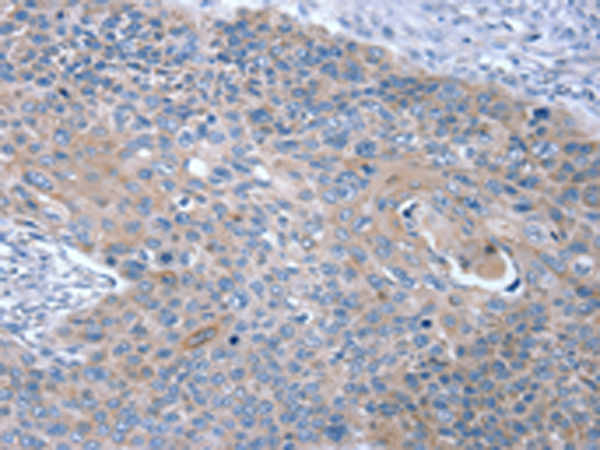

分类: 科研抗体货号: P08794别名: MRT1; MY014应用: IHC反应种属: Human, Mouse, Rat